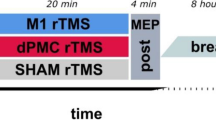

All participants took part in two experimental sessions each corresponding to performing the motor sequence learning task with either one of both hands. Each session encompassed two parts, a training part in the morning at 11 am and a delayed retest part 8 h later (7 pm) to assess consolidation of training-induced task skill acquisition. Sessions were separated by at least 14 days to prevent carry-over effects. In patients with unilateral cerebellar lesion, the order of sessions was balanced with respect to practicing with the ipsilesional or contralesional hand. In healthy controls and patients with bilateral lesions, the order of sessions was counterbalanced with respect to practicing with the dominant or non-dominant hand. Before each training and each retest, alertness of participants was assessed with the Stanford Sleepiness Scale [28].

Motor sequence performance was assessed by an adapted version of the sequential finger tapping task introduced by Karni and colleagues [4], which has also been employed extensively in our laboratory [29,30,31]. In each of both experimental sessions, participants were asked to practice one of two different, equally difficult five-element finger-tapping sequences on a four-button customized keyboard. Sequence 1 was “4-1-3-2-4” and sequence 2 was “1-4-2-3-1” (1 = index finger, 2 = middle finger, 3 = ring finger, 4 = little finger). The order of type of sequence allocation to session 1 or session 2 was balanced across all participants. To verify that participants had explicit knowledge of the finger-tapping sequence prior to training onset, they were required to slowly repeat the sequence until they reproduced it three times in a row without mistakes. The training part encompassed 14 successive blocks of sequence execution which were separated by 25-s rest periods. Participants were instructed to perform the sequence as fast as possible while making as few errors as possible. Unbeknownst to the participants, each task block was terminated after 60 key presses to make sure that all participants performed the same number of training movements (i.e., all participants received the same amount of training). Therefore, a maximum of 12 correct sequences could be executed within each block of training. The beginning of a training block was indicated by a green fixation cross in the middle of a computer screen in front of the participants, which turned red (i.e., after 60 button presses on the keyboard) to indicate the beginning of a 25-s rest block. The delayed retest session after an interval of 8 h encompassed only 4 blocks of the task. During training and retesting no information on the sequence was presented to the participants (Fig. 1).

Experimental design. a Finger positioning on the keyboard and sequence order exemplary for the right hand. b The experiment consisted of two sessions which were separated by at least 14 days. Each session contained a training phase and a delayed retest phase. Training (11 am) encompassed 14 task blocks of 60 key presses and 25-s rest periods in-between blocks. Delayed retesting took place 8 h later (7 pm) and encompassed 4 blocks of the task